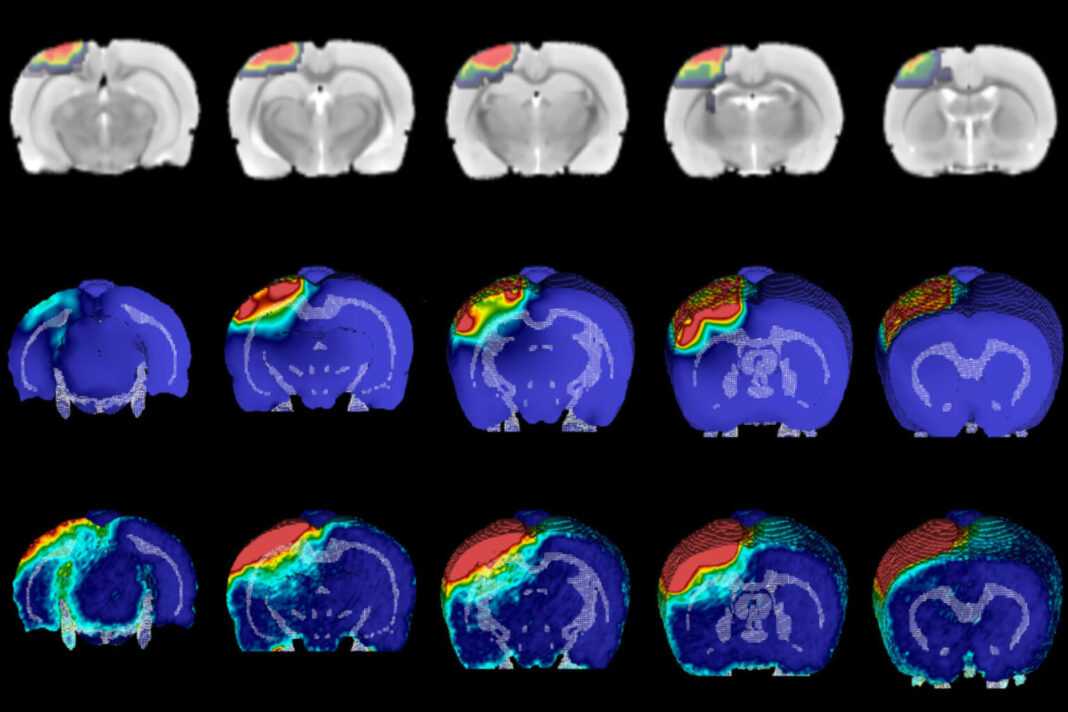

Μία από τις μεγαλύτερες προκλήσεις για τους νευροεπιστήμονες ήταν η πλήρης κατανόηση του τρόπου με τον οποίο μια TBI αλλάζει τη διασταυρούμενη συζήτηση μεταξύ διαφορετικών κυττάρων και περιοχών του εγκεφάλου. Στη νέα μελέτη, οι ερευνητές βελτίωσαν μια διαδικασία που ονομάζεται iDISCO, η οποία χρησιμοποιεί διαλύτες για να κάνει τα βιολογικά δείγματα διαφανή. Η διαδικασία αφήνει πίσω έναν πλήρως άθικτο εγκέφαλο που μπορεί να φωτιστεί με λέιζερ και να απεικονιστεί σε 3D με εξειδικευμένα μικροσκόπια. Με τις βελτιωμένες διαδικασίες εκκαθάρισης του εγκεφάλου, η ομάδα UCI χαρτογράφησε τις νευρικές συνδέσεις σε ολόκληρο τον εγκέφαλο. Οι ερευνητές εστίασαν στις συνδέσεις με ανασταλτικούς νευρώνες, επειδή αυτοί οι νευρώνες είναι εξαιρετικά ευάλωτοι στο θάνατο μετά από έναν εγκεφαλικό τραυματισμό. Η ομάδα εξέτασε αρχικά τον ιππόκαμπο, μια περιοχή του εγκεφάλου που είναι υπεύθυνη για τη μάθηση και τη μνήμη.

Στη συνέχεια, ερεύνησαν τον προμετωπιαίο φλοιό, μια περιοχή του εγκεφάλου που συνεργάζεται με τον ιππόκαμπο. Και στις δύο περιπτώσεις, η απεικόνιση έδειξε ότι οι ανασταλτικοί νευρώνες αποκτούν πολύ περισσότερες συνδέσεις από γειτονικά νευρικά κύτταρα μετά την TBI, αλλά αποσυνδέονται από τον υπόλοιπο εγκέφαλο. “Γνωρίζουμε εδώ και πολύ καιρό ότι η επικοινωνία μεταξύ διαφορετικών εγκεφαλικών κυττάρων μπορεί να αλλάξει πολύ δραματικά μετά από έναν τραυματισμό”, δήλωσε ο Robert Hunt, PhD, αναπληρωτής καθηγητής ανατομίας και νευροβιολογίας και διευθυντής του Κέντρου Ερευνών Επιληψίας στο UCI School of Medicine του οποίου εργαστήριο διεξήγαγε τη μελέτη, “Αλλά, δεν μπορέσαμε να δούμε τι συμβαίνει σε ολόκληρο τον εγκέφαλο μέχρι τώρα”.

Για να ρίξουν μια πιο προσεκτική ματιά στις κατεστραμμένες εγκεφαλικές συνδέσεις, ο Hunt και η ομάδα του επινόησαν μια τεχνική για την αντιστροφή της διαδικασίας καθαρισμού και την ανίχνευση του εγκεφάλου με παραδοσιακές ανατομικές προσεγγίσεις. Τα ευρήματα έδειξαν εκπληκτικά ότι οι μακριές προβολές των απομακρυσμένων νευρικών κυττάρων εξακολουθούσαν να υπάρχουν στον κατεστραμμένο εγκέφαλο, αλλά δεν σχημάτιζαν πλέον συνδέσεις με ανασταλτικούς νευρώνες.

“Φαίνεται ότι ολόκληρος ο εγκέφαλος επανασυνδέεται προσεκτικά για να αντιμετωπίσει τη ζημιά, ανεξάρτητα από το αν υπήρξε άμεσος τραυματισμός στην περιοχή ή όχι”, εξήγησε ο Alexa Tierno, μεταπτυχιακός φοιτητής και συν-πρώτος συγγραφέας της μελέτης. “Αλλά διαφορετικά μέρη του εγκεφάλου πιθανότατα δεν συνεργάζονται τόσο καλά όσο πριν από τον τραυματισμό”. Οι ερευνητές θέλησαν στη συνέχεια να προσδιορίσουν εάν ήταν δυνατό οι ανασταλτικοί νευρώνες να επανασυνδεθούν με απομακρυσμένες περιοχές του εγκεφάλου. Για να το ανακαλύψουν, ο Hunt και η ομάδα του μεταμόσχευσαν νέους ενδονευρώνες στον κατεστραμμένο ιππόκαμπο και χαρτογράφησαν τις συνδέσεις τους, με βάση την προηγούμενη έρευνα της ομάδας που δείχνει ότι η μεταμόσχευση ενδονευρώνων μπορεί να βελτιώσει τη μνήμη και να σταματήσει τις επιληπτικές κρίσεις σε ποντίκια με TBI.